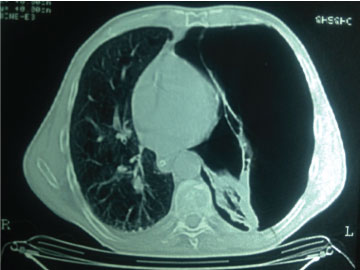

In the first two tomographic cuts the presence of pneumothorax is evident, in the third cut the presence of contact of both pleura is documented, an ultrasonographic sign called the pulmonary point. In the remaining sections, 4th and 5th same image. Observe in all tomographic sections the displacement of the mediastinum to the right hemithorax, which may cause tension pneumothorax (Figure 2, Figure 3, Figure 4, Figure 5 and Figure 6).

Figure 2: Evident Pneumothorax in left hemithorax.

Figure 3: Pneumothorax in the left hemithorax.